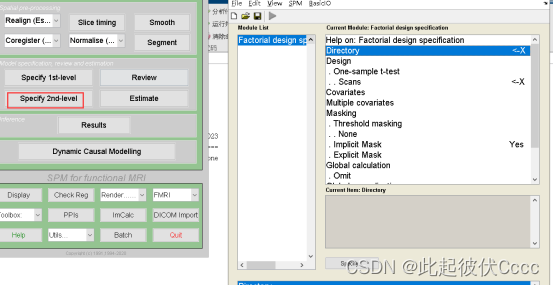

3.1 生成设计矩阵

(1)点击上图中的圈1(Specify 2nd-level)按钮,进入以下界面:

(2)双击Directory,这个是需要你选择你的输出结果放置的文件夹

(3)点击Design,选择two-sample t-test,接下来给Group 1 scans和Group 2 scans导入被试的结构特征数据。

以TIV(之前在2.4步保存的文件)、年龄、性别作为协变量回归。(注意顺序)